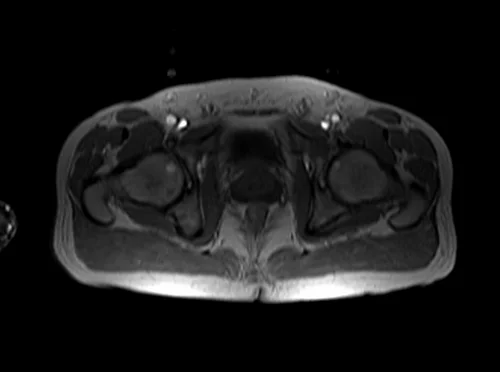

Unlock MRIMaster Offline & Ad-Free for $10